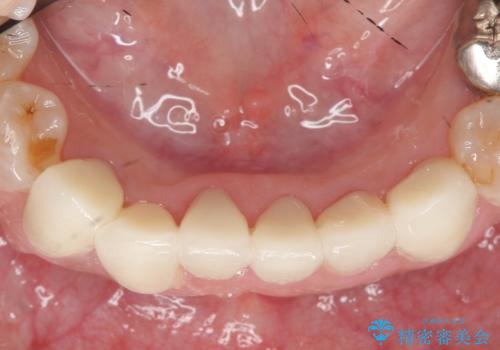

下顎は左側 4 番目から右側 4 番目までの 8 歯と左下 567 ブリッジをオールセラミッククラウンで補綴し、右下67の銀歯はセラミックインレーによる修復を行いました。